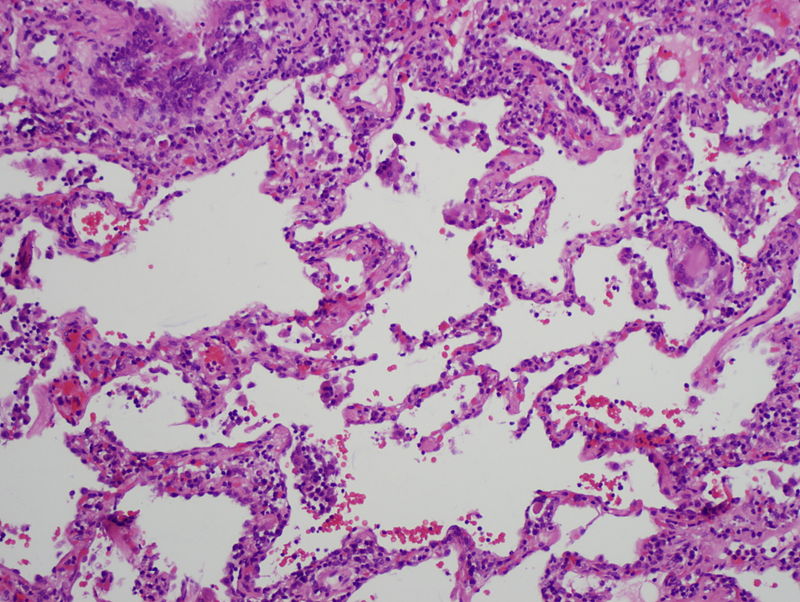

Pneumoconiosis is the form of interstitial fibrosis caused by occupational exposure to fibrogenic particles like asbestos, beryllium, and silica dusts.

The alveolar macrophages in the lungs engulf these particles inducing fibrosis.